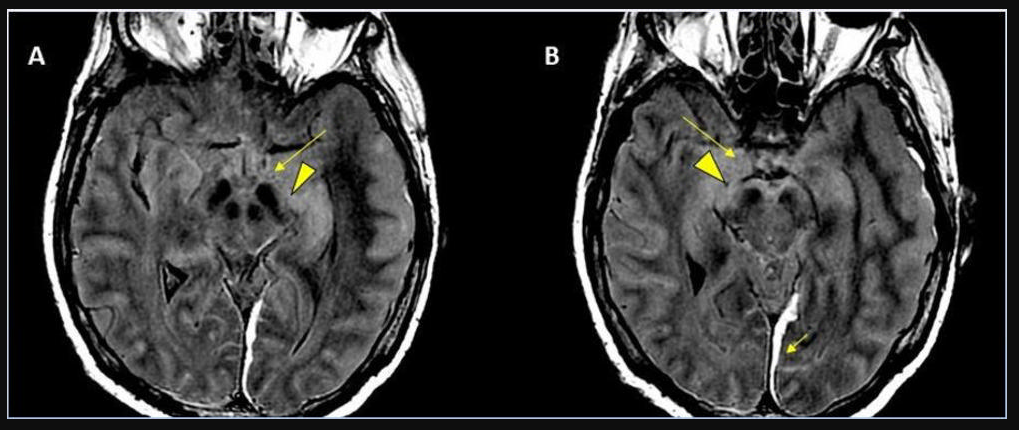

This photo gallery shows the variety of radiological presentations of COVID-19 (SARS-CoV-2) in medical imaging, including computed tomography (CT), radiograph X-rays, ultrasound, echocardiograms and magnetic resonance imaging (MRI). The radiology images show examples of typical COVID pneumonia in the lungs and the numerous complications the virus causes in the body in multiple organs, including the brain, kidneys, heart, abdomen and vascular system.

Ultrasound, especially hand-held ultrasound imaging devices, have become a primary imaging modality for novel coronavirus because of the ease to bag the device and sterilize it after use. CT and mobile X-ray systems are also used as front-line imaging systems for COVID-positive or suspected COVID patients.